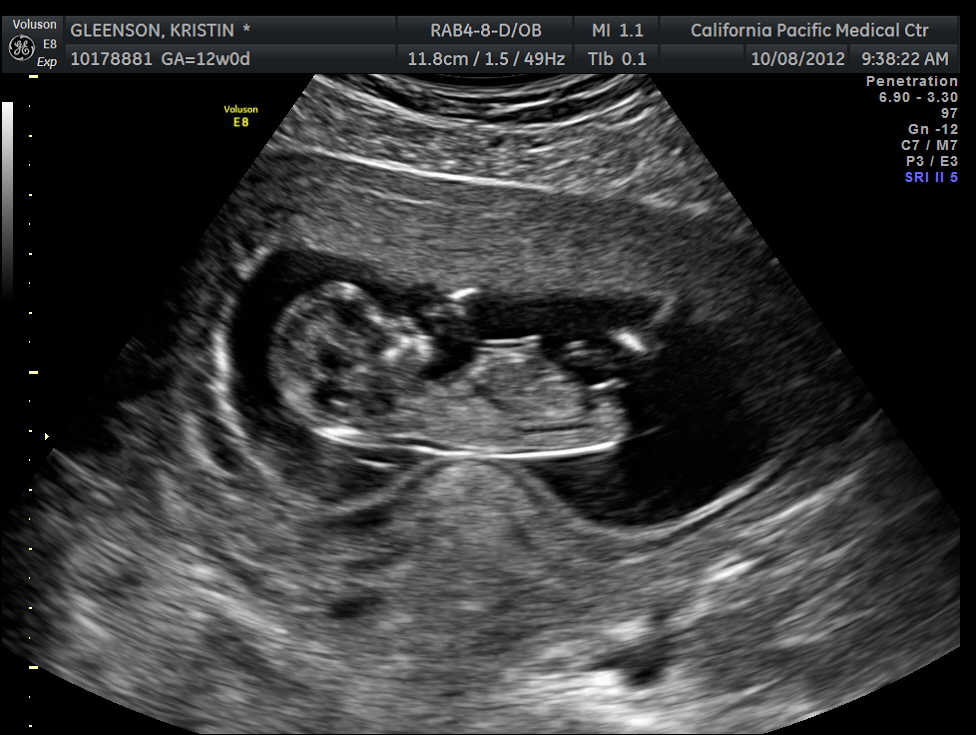

12 week US boy or girl????